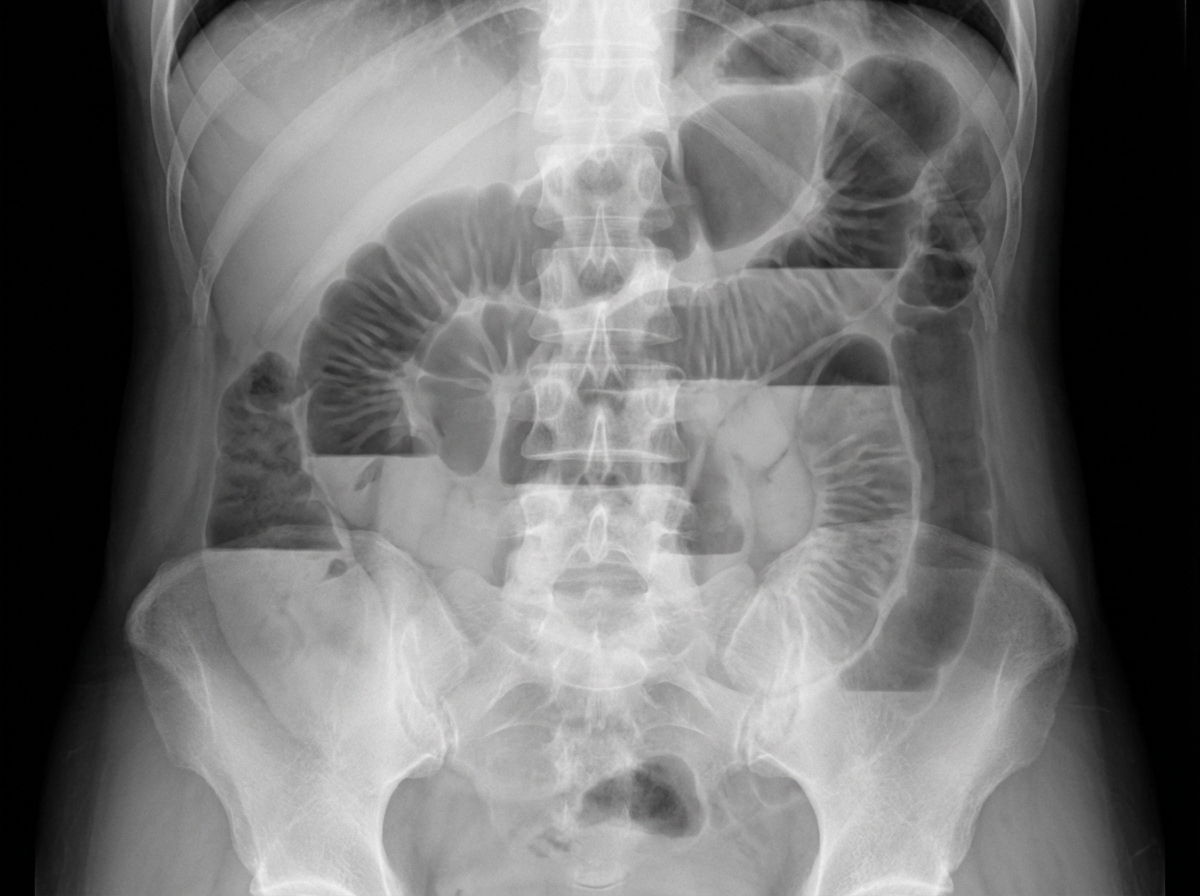

A 30-year-old patient presents with acute abdominal pain and obstipation. An X-ray is provided. What is the most likely diagnosis?

Explanation: ***Small bowel obstruction*** - Classic X-ray findings include **central dilated small bowel loops** with **valvulae conniventes** (complete mucosal folds) and **stepladder air-fluid levels**. - **Paucity of colonic gas** distally is characteristic, as obstruction prevents bowel contents from reaching the colon. *Large bowel obstruction* - X-ray shows **peripheral dilated colonic loops** with **haustrations** (incomplete mucosal folds), not central small bowel dilation. - **Cecal dilation** is often prominent, and small bowel may appear normal or minimally dilated. *Gastric outlet obstruction* - X-ray typically shows **marked gastric distension** with a **dilated stomach** containing air-fluid levels. - **Minimal small bowel gas** is present, as obstruction occurs at the **pylorus** or **duodenum**. *Duodenal atresia* - Characteristic **double-bubble sign** on X-ray showing dilated **stomach** and **proximal duodenum**. - This condition occurs in **neonates**, not 30-year-old patients, and presents shortly after birth.